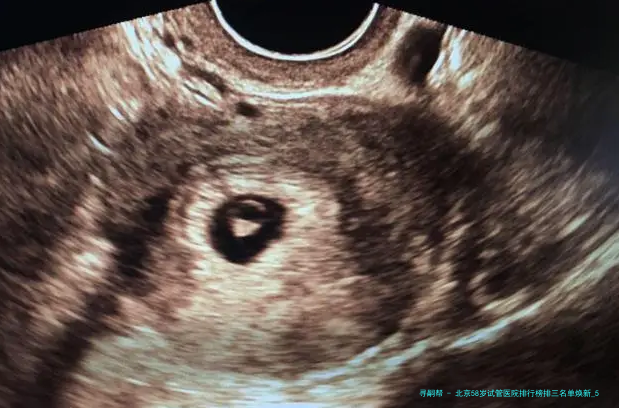

“医生,我58岁AMH值几乎为零,仍旧有可能用自己的卵子做试管吗?”在北京某生殖中心咨询室,一位鬓脚花白的女士紧握化验单的手悄悄发抖——这便是很多超高龄家庭求子路的真实缩影💔。58岁生育堪称“逆天改命”🧬:卵巢功效彻底衰竭、胚胎染色体不同寻常率超80、妊娠并发症风险迅猛上涨……选错医院不仅人财两空,更可能错失后的生育机会!2025年北京具备试管资质的医院达18家,但真实擅长超高龄方案的仅寥寥数家。本文结合新临床数据,揭晓严选前三医院排行、反转策略与性价比方案,让每一分盼望都用在刀刃上!

58岁试管成功的重要在于医院是否拥有个别化促排方案、胚胎基因学筛查(PGT)技术、多科目并发症处理能力。根据2025年北京市辅助生殖质量报告,下面列举三家医院在超高龄领域表现突出(按技术储备、临床数据、患者口碑综合排序):

答:核心差异在于胚胎质量、子宫容受性、个体化方案三重因素。2025年份限制据表现,58岁病患胚胎染色体异常率超85,但通过三代试管PGT筛查可以筛选除90异常胚胎,将临床妊娠率从5提升高到15以上。